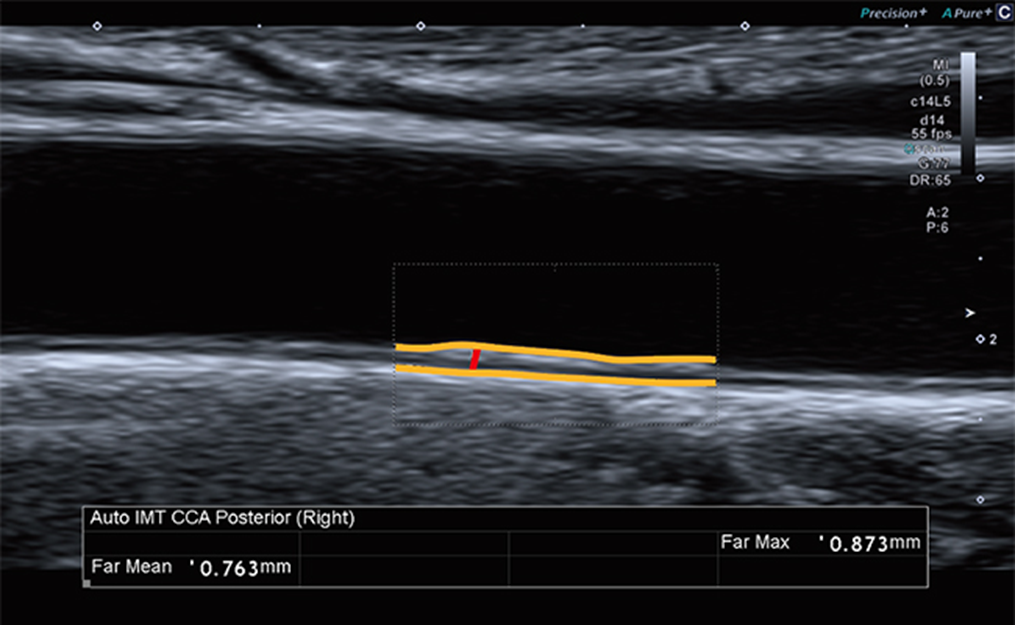

Phép đo IMT động mạch cảnh tự động cho phép bạn thực hiện đo đạc nhanh chóng và ổn định ngay khi hình ảnh bị nhiễu, làm cho phép đo trở nên đơn giản. Bạn có thể đo độ dày dễ dàng hơn.